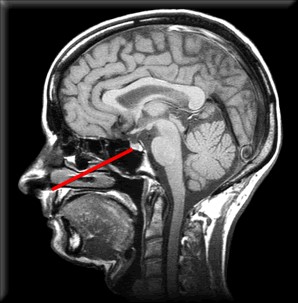

L’hypophyse est une glande située à la base du crâne.

Hypophyse

La chirurgie par approche transsphénoïdale

La chirurgie prévue s’appelle : Exérèse d’une tumeur par approche transsphénoïdale (ou par abord endonasal).

Elle consiste à retirer la tumeur en passant par le nez.

Une incision est pratiquée dans le nez (vous n’aurez donc pas de plaie ou de cicatrice visible). Ensuite, le sinus sphénoïdal est traversé pour atteindre la tumeur. La tumeur est retirée.